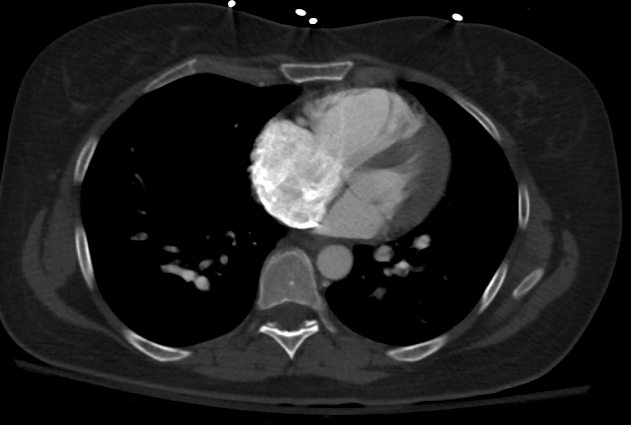

Right ventricular dysfunction can be assessed objectively by electrocardiography, echocardiography, computed tomogrpahy or by elevated brain natriuretic peptide. Examples of electrocardiographic signs of right ventricular strain include new right bundle branch block and antero-septal ST segment changes. The most specific sign of pulmonary embolism related right ventricular dysfunction on echocardiography is McConnell sign. McConnell sign is normal apical movement with mid-wall akinesia.

Other echocardiographic signs of right ventricular strain include right ventricular dilatation, new onset tricuspid regurgitation, septral flattening, lack of respiratory variation of the IVC and right ventricular hypokinesia. Computed tomogrpahic signs of right ventricular dysfunction include ventricular dilatation, contrast filling the IVC, dilatation of the main pulmonary artery and septal flattening. Myocardial necrosis is diagnosed by elevated troponin.